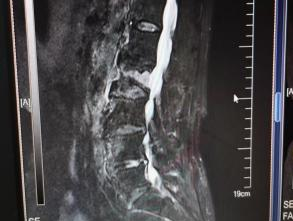

为提升区域内基层医疗机构糖尿病足诊疗服务能力、促进青年医师对糖尿病足的规范化诊治水平,遵义市第二城市医疗集团总院(贵州航天医院)圆满举办贵州省继续医学教育项目——胫骨横向骨搬移技术治疗糖尿病足专题研讨班。 贵州航天医院党委委员、副院长彭亮出席会议并致辞,遵义市第二城市医疗集团各成员单位,以及红花岗区、汇川区、绥阳县、桐梓县等多个区县的基层医疗机构骨干医师参加会议。 研讨班 本次研讨班以胫骨横向骨搬移技术在糖尿病足治疗中的应用为核心主题,围绕糖尿病药物治疗与生活方式管理策略、围手术期血糖精准调控要点、胫骨横向骨搬移技术典型病例深度解析、糖尿病足的临床分型与个体化治疗方案制定等临床实践中的热点与难点展开深入探讨,通过专题授课、案例研讨、互动交流等多元化形式,为参会者搭建了理论与实践结合的学习平台。 此次研讨班不仅为区域内基层医院搭建了学术交流与经验共享的平台,更对推动糖尿病足预防、诊断与治疗的规范化、系统化发展起到了积极作用,有效助力青年医师更新专业知识体系、提升临床技能,为进一步保障区域内糖尿病足患者的健康奠定了坚实基础。 贵州航天医院骨科专家简介 陈明勇 骨一科主任,副主任医师 临床擅长:从事创伤骨科工作约20年,对骨缺损、骨不连、骨肿瘤、肢体畸形等的肢体矫形重建及功能重建,慢性化脓性骨髓炎的根治治疗、糖尿病足的保肢治疗、快速康复理念(ERAS)下的老年骨折的诊治,四肢复杂骨折的诊治,四肢骨折等微创手术治疗具有丰富的临床经验。 2004年毕业于遵义医学院临床专业,曾在中国人民解放军总医院、广西医科大学第一附属医院、上海第六人民医院骨科进修。中国中西医结合学会骨伤科专业委员会横向骨搬移治疗糖尿病足及微血管网再生学组首届委员,遵义市医学会创伤分会常务委员。 瞿 晖 骨科党支部书记,骨二科主任,副主任医师 临床擅长:对骨科的常见病、关节外科、脊柱外科及运动医学疾病的诊治具有丰富的临床经验,熟练掌握骨科手术操作技术。 毕业于遵义医学院临床医学系,2005年前往广州中山大学第一附院骨显微医学部进修学习,2011年前往成都华西医院进修学习,并多次在省内外学习骨科相关知识,是中华医学会骨科分会会员。 赵小锋 中共党员,骨二科副主任,副主任医师 临床擅长:从事骨科临床工作11年,对骨科常见病、多发病诊疗有较为丰富的临床经验,擅长脊柱相关疾病诊断及治疗,尤其是颈、腰、腿疼痛疾病诊断及治疗,擅长胸腰椎骨折微创经皮穿刺内固定术、经皮穿刺椎体成形术、经皮穿刺脊柱内镜下腰椎间盘摘除术、单纯开创腰椎间盘摘除术、腰椎滑脱复位椎间植骨椎融合内固定术、腰椎管狭窄减压融合内固定术及人工髋、膝关节置换术等。 2012年毕业于遵义医学院外科学专业硕士研究生,2019年参加“遵义市115医学人才精英计划”于上海交通大学第一附属医院培训学习,2023年于北京大学第三人民医院脊柱外科进修学习,曾获得遵义市优秀医师荣誉称号。 遵义市手外科第一届委员,遵义市医学会创伤分会第一届委员,遵义市医学会创伤分会第二届委员,贵州省康复医学会第三届脊柱脊髓专业会委员,遵义市医学会烧伤与整形外科学分会委员,发表论文5篇,其中国家级核心期刊1篇,SCI论文1篇,主持市级课题1项并结题,参与市级课题2项。 赵兴东 骨科主任医师 临床擅长:擅长骨科的常见病及各种创伤、四肢骨折创伤修复、骨感染、手足疾病的诊治和手足体表畸形的矫形整复,熟练掌握骨科四肢骨病及创伤的手术操作技术,尤其在四肢关节复杂性损伤、手足外伤、组织缺损创面、难治创面的皮瓣修复方面及平足、高弓足矫形方面及四肢慢性疼痛诊治、康复方面具有丰富的临床经验。 硕士研究生,毕业于遵义医学院临床外科系,2015年前往山东省立医院手足外科进修学习;遵义市医学分会创伤分会第一、二届委员,遵义市手外科医学会第二委届员会常务委员;在省级及省级以上期刊发表文章9篇,参编著作2部,参与主持并完成市级课题1项,参与市级课题2项、省级课题1项。 张艳金 中共党员,骨科副主任医师 临床擅长:从事骨外科工作16年,对复合伤、多发伤的救治、四肢骨干骨折、关节周围骨折、骨肿瘤、骨髓炎等诊治具有丰富的临床经验。 中共党员,硕士研究生,2006年本科毕业于山西医科大学第二临床医学院,2011年研究生毕业于北京军区总医院;在“老年COPD患者合并髋部骨折的诊治”国际合作课题组研究两年,在老年髋部骨折的诊治方面具有丰富的经验,并发表论文6篇;主持遵义市级课题1项,承担遵义医科大学的临床教学工作,获得遵义医科大学优秀带教老师荣誉。编撰有《骨科疾病诊疗精粹》一书,开展2项新技术,编撰地方规范《务川自治县创伤骨科常见疾病诊疗规范》一书。 张俊凯 骨科副主任医师 临床擅长:从事骨科临床工作28年,对创伤骨折、骨感染、骨缺损、骨不连等外科诊治,四肢骨折的微创手术治疗,四肢复杂骨折(如关节内粉碎性骨折、多发骨折等)的损伤控制及手术治疗等具有丰富的临床经验。 1995年毕业于遵义医学院临床专业,2009年前往复旦大学附属医院骨科进修1年。 卢懿明 中共党员,骨科副主任医师 临床擅长:从事骨科工作18年,对创伤骨折、四肢骨折的微创手术治疗、四肢复杂骨折(如关节内粉碎性骨折、多发骨折等)的损伤控制及手术治疗,尤其是髋部骨折的PFNA等微创技术,踝关节骨折、膝关节周围骨折的Mipo微创技术等具有丰富的临床经验,开展了4项新技术,发明6项新型专利技术。 2005年毕业于遵义医学院临床专业,2017年,前往南方医科大学第三附属医院骨科进修半年,回院后运用Mipo技术对骨干骨折及干骺端骨折的治疗技术,同时积极开展骨盆骨折、髋臼骨折腹直肌外侧切口的应用;发表了多篇专业论文,经常参与省内外学术交流会授课,获得医院荣誉称号多个。 邬夏荣 骨科副主任医师 临床擅长:从事骨科工作16年,对四肢复杂骨折、骨肿瘤的诊治,尤其是足踝创伤、慢性踝关节损伤、平足症等诊疗具有丰富的临床经验。 2006年毕业于遵义医科大学临床医学专业,曾在陆军军医大学西南医院进修学习,发表多篇骨科学术论文。 余德怀 中共党员,骨科副主任医师 临床擅长:从事骨科工作10余年,对运动医学、骨关节、脊柱外科常见病、多发病的诊治具有丰富的临床经验。 硕士研究生,2011年毕业于遵义医学院临床医学专业,曾前往遵义医科大学附属医院运动医学专业进修学习;是贵州省医学会运动医学分会青年委员,西部关节镜联盟委员;发表多篇骨科学术论文。 冯 乾 骨科副主任医师 临床擅长:从事骨科工作近20年,熟练掌握骨科多发病及常见病的诊治,尤其对脊柱退变性疾病的诊断及治疗具有丰富的临床经验,主要研究脊柱微创相关治疗方式,能熟练开展椎间孔镜及UBE。 曾前往北京大学第三医院进修学习疼痛及椎间孔镜、首都医科大学友谊医院专业进修脊柱内镜;是贵州省康复医学会第三届脊柱脊髓专业委员会委员;发明专利3项、发表脊柱外科专业论文多篇。 贵州航天医院骨科简介 基本情况 贵州航天医院(原3417医院)骨科组建于1968年,前身是以创伤和断肢(断指)再植闻名于世的上海市第六人民医院骨科,中国断肢(断指)再植的奠基者、中科院院士陈仲伟等专家莅临科室指导医疗和教学,并在70年代开展了贵州省首例断肢(断指)再植手术。组建50余年来,诊治患者已逾百万,挽救了无数的伤病员,成为了保障遵义地区人民群众健康的重要支撑。 经过几代人的不懈努力,今天的骨科,已由创伤骨科发展至骨病、骨肿瘤、骨结核等领域,现有脊柱外科、关节外科、四肢创伤、手足外科四个亚专科,成为了集医疗、教学、科研于一体的综合学科,是贵州省临床重点专科、遵义市临床重点专科、遵义市骨科临床医学中心、遵义市基层骨科专科联盟理事长单位。 科室目前开放床位110张,共有医护人员50余人,副高级以上专家18人,硕士研究生15人。拥有一流骨科医疗设备多台,每年不定期选派优秀技术骨干到全国各大知名医学院校进修、学习、参观、交流,并邀请国内、国外知名专家教授来院进行交流、指导,通过不断引进国内外先进的诊疗技术,科室医疗技术水平稳步提升,为广大人民群众提供了优质的医疗服务。 专科特色 骨一科 (一)骨缺损、骨不连的肢体与功能重建 胫骨横向骨搬移技术治疗糖尿病足: (二)慢性骨髓炎的根治治疗 (三)肢体缺血性疾病如糖尿病足、脉管炎的保肢治疗 (四)皮瓣修复 (五)复杂创伤的治疗 (六)老年髋部骨折及小儿骨折快速手术 老年髋部骨折: 骨二科 (一)胸腰椎骨折微创经皮椎弓根螺钉固定术 (二)老年性骨质疏松性患者腰椎滑脱脊柱内固定术(骨水泥螺钉) (三)V形双通道脊柱内镜技术(VBE)腰椎融合术治疗腰椎退行性疾病 (四)老年性骨质疏松性骨折(PVP/PKP)术 (五)人工髋关节置换术 (六)双侧股骨头坏死人工全髋关节置换 (七)右侧全髋置换术后假体周围骨折翻修 (八)人工膝关节置换术 (九)人工膝关节假体松动翻修 (十)关节镜技术 传统手术切口 关节镜技术切口 诊疗范围 骨一科 1.四肢创伤、矫形。 2.手、足踝外科。 骨二科 End